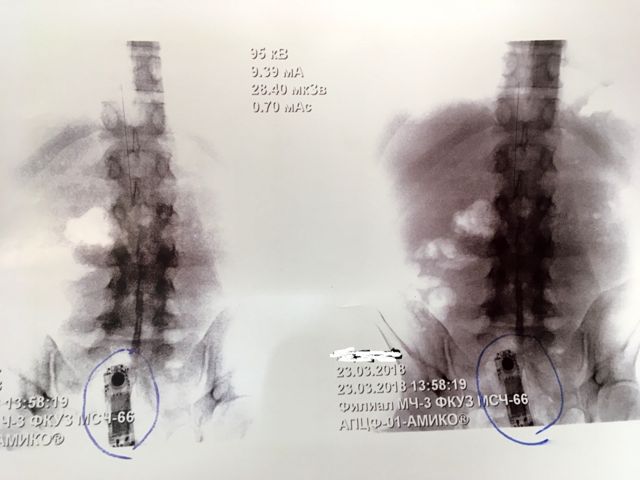

Сотрудники краснотурьинской исправительной колонии строго режима ИК-3 поймали заключенного с телефоном в прямой кишке, сообщили в пресс-службе ГУФСИН по региону.

Фото: Пресс-служба ГУФСИН России по Свердловской области